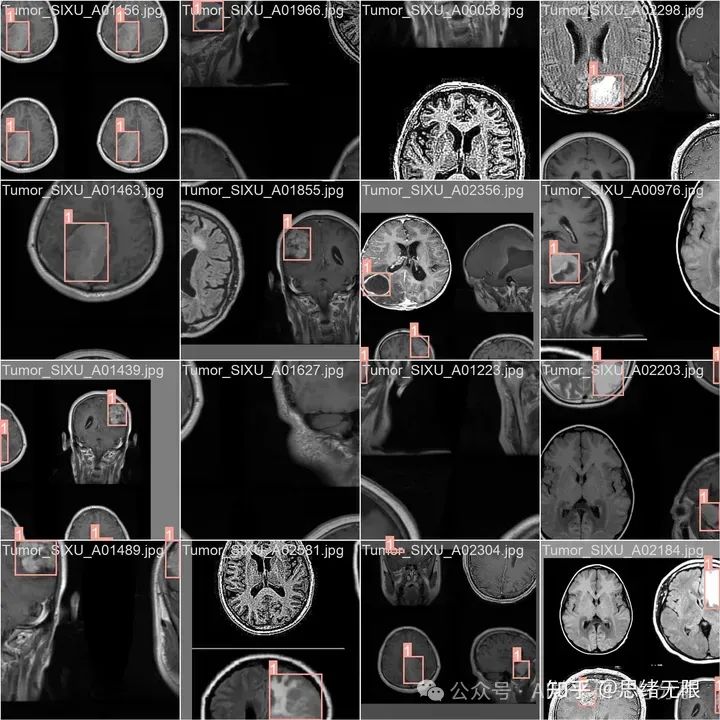

在本研究中,我们专门为训练和评估基于YOLOv8算法的癌症图像检测模型而设计,包含了3076张图像,其中包括2634张用于训练的图像、301张用于验证的图像,以及141张用于测试的图像。这一细致的分配确保了模型能够在足够大的数据集上进行训练,同时拥有独立的测试集和验证集,以评估模型的性能和泛化能力。

在数据预处理方面,我们采取了一系列标准化步骤来确保数据集的一致性和可用性。所有图像均经过自动方向调整处理,确保了图像方向的统一性,并去除了EXIF方向信息,消除了由于拍摄角度不同可能带来的变量。此外,考虑到YOLOv8算法的输入要求,所有图像均被调整至416x416像素的尺寸。这种统一的尺寸不仅有利于算法处理,也有助于减少模型训练和推断过程中的计算开销。

通过对数据集标签的分析,我们发现了一些关键的特征。数据集的实例主要分为两大类:良性和恶性肿瘤。在实例数量上,恶性肿瘤的数量远超过良性,这可能是因为研究的重点是更有效地检测癌症。然而,这种不平衡的分布也提示我们,在训练过程中可能需要使用特定的技术来解决类别不平衡的问题,如调整类别权重或应用过采样技术。

进一步分析边界框的大小和分布,我们发现恶性肿瘤的边界框在大小上相对一致,而良性肿瘤的边界框则呈现出较大的变异性。这可能意味着恶性肿瘤在成像上表现出较为规律的形状和尺寸,而良性肿瘤则在形态上更加多样。这一发现对于设计模型的检测窗口和锚框策略至关重要。

边界框的空间分布分析揭示了数据集中的实例在图像内的分布均匀,这有助于模型学习到在不同位置检测肿瘤的能力。同时,边界框的宽度和高度分布显示出大部分肿瘤在图像中占据较小的区域,这对于设置检测模型的分辨率和感受野具有指导意义。博主使用的类别代码如下:

Chinese_name = {'Benign': "良性", 'Tumor': '肿瘤'}

总之,我们介绍的数据集经过精心设计和预处理,以适应癌症图像检测模型的需求。数据集的类别分布、边界框的大小和形状、以及空间位置的多样性,都是在设计和训练YOLOv8模型时必须要考虑的因素。通过充分利用这些特性,我们能够提高模型的泛化能力和检测精度,进一步推动癌症检测领域的研究和应用发展。